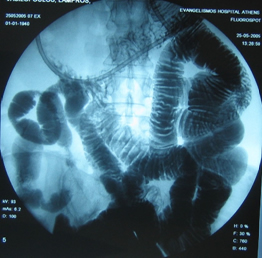

Στους ίδιους ασθενείς η εντερόκλυση μπορεί να αναδείξει ανάλογα ευρήματα με την ενδοσκοπική κάψουλα (εικόνες 36-43) ή να είναι φυσιολογική (εικόνες 44-48).

36  37

Εικόνες 36, 37. Ο ίδιος ασθενής με τις εικόνες 15, 16. Εικόνα πλακόστρωτου με στένωση και παρουσία        βαθιάς εξέλκωσης του βλεννογόνου